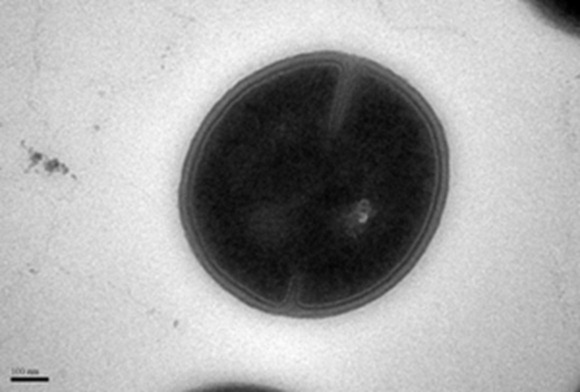

Figure 1: Transmission Electron Microscope (TEM) image of the MRSA cell before treatment.

To address this increasingly widespread healthcare problem, the global research community has been investigating the use of synthetic polymers with antimicrobial properties to overcome the drawbacks of the antibiotic delivery mechanism. Conventional antibiotics penetrate the microorganisms without damaging the bacteria structure (cell wall and membrane). Hence, the bacteria can easily develop resistance against these drugs. In comparison, antimicrobial polymers break down the bacterial cell wall and membrane based on electrostatic interaction with the bacteria to prevent drug resistance.